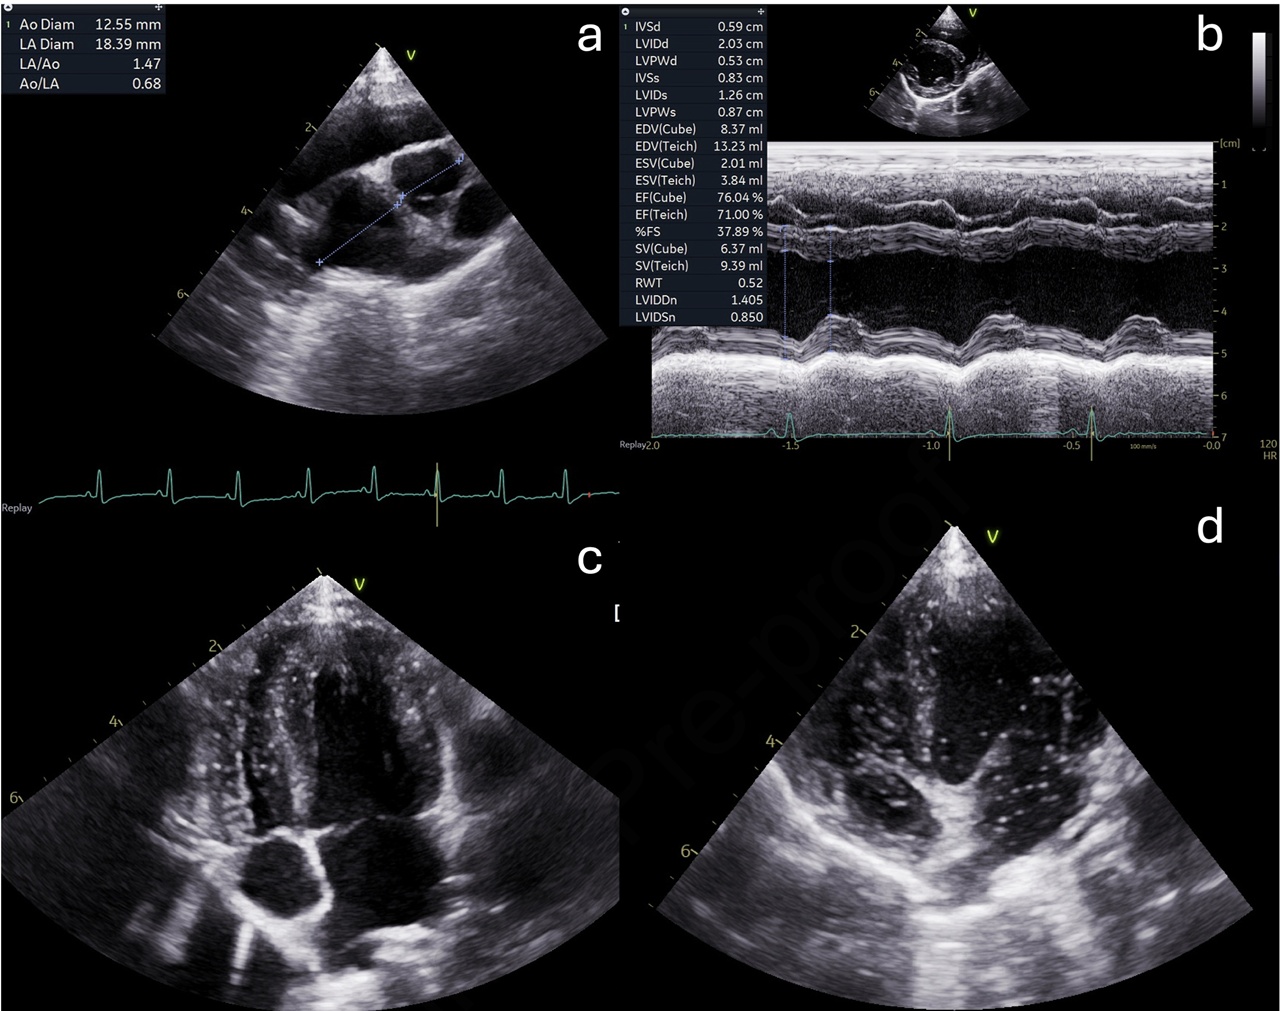

위 초음파 그림이 대표적인 사례다. 이 반려견은 정기적인 심초음파 검사에서 이상이 발견되지 않았다. (a)에서 LA/Ao 비율이 정상인 것을 알 수 있고, (b)에서 LVIDDN이 정상인 점도 확인할 수 있다. 하지만, (d)에서 bubble study에서 우심방과 우심실뿐만 아니라 좌심방과 좌심실에서도 상당한 조영제(미세기포)가 확인됐다.